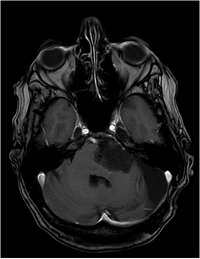

Epidermoid - Flair - axial

Fehlendes Liquorsignal als Signalsteigerung

DD: Arachnoidalzyste, mit  Liquorsignal in allen Sequenzen